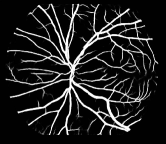

Refer to caption

Figure 1: Vessel segmentation results of side-output(s-out) layers produced by three networks. From top to bottom the network is normal DSN (with no short connections), BS-DSN (DSN with bottom-top short connections) and BTS-DSN (DSN with both bottom-top and top-bottom short connections), respectively.

As pointed out in recent works [15, 17], a good semantic segmentation network should learn multi-level features. Further, it should have multiple stages with different receptive fields to learn more inherent features from different scales. FCN, taken as an example, uses skip connections to fuse multiple stages outputs, as well as the HED network, in which a series of side-output layers are added after each stage in VGGNet. The HED network was first proposed for edge detection, and further used for image-level vessel segmentation in recent studies [6, 16], with significant performance. However, our experimental results show that such network architecture is not appropriate for vessel segmentation directly. Figure 1 provides such an illustration. Reasons for this phenomenon are straightforward. On one hand, the side-output of the first layer often contains too many noises. On the other hand, the features produced by the last side-output layer are too coarse due to information loss of pooling operation. Obviously, the inaccurate vessel map of side-output1 and side-output4 should have negative impacts on the final segmentation result.

In addition, we can observe from Figure 1 that the side-output1 and side-output4 of the BTS-DSN were more accurate compared with those of the DSN.